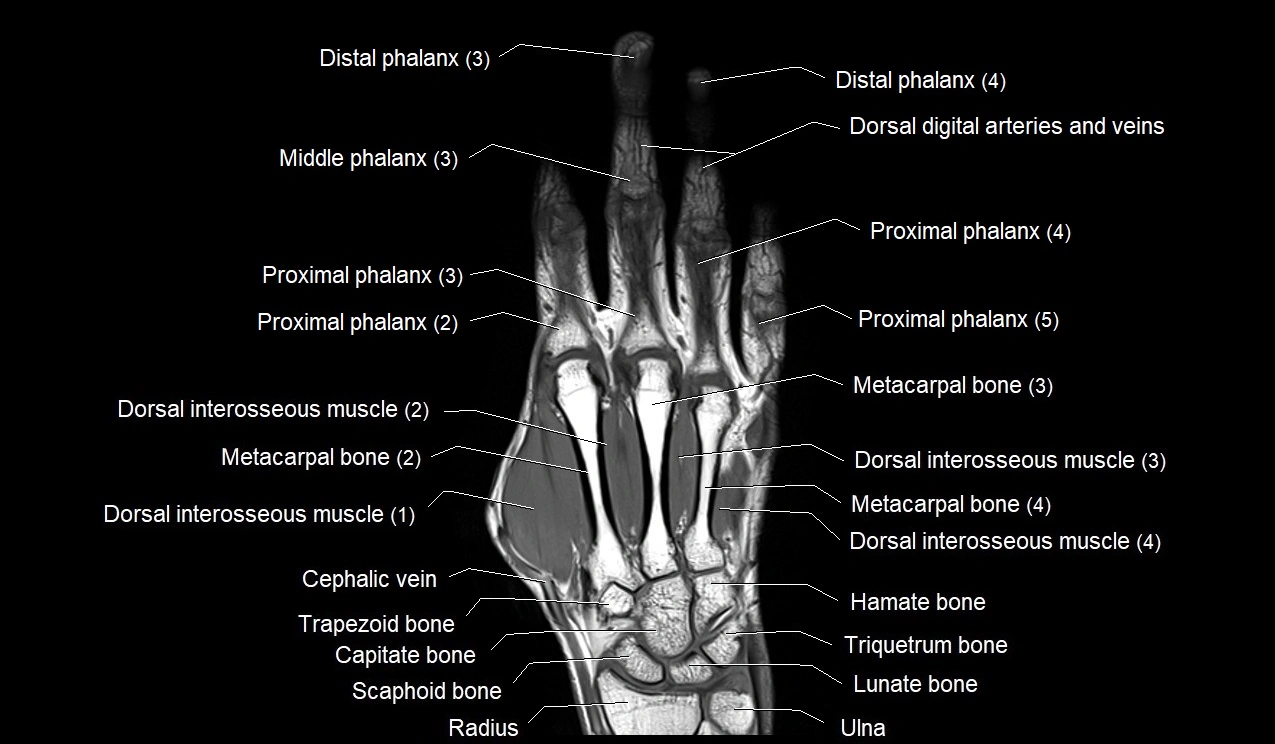

MRI image